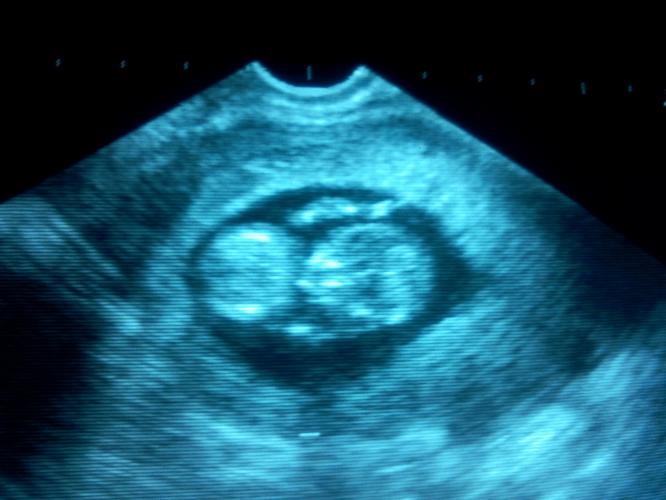

“Kunt u een beetje naar beneden schuiven mevrouw, dan gaan we eens kijken wat er aan de hand is”…… niet twee minuten later kijken mijn man en ik elkaar aan….is dat…een hartslag? De gyneacoloog draait het scherm naar ons toe “Kijk zegt ze, dit is het hoofdje, dit zijn de armpjes en beentjes, u bent 11 weken zwanger”

Daar was je dan lieve jongen (al wisten we toen nog niet dat je een jongetje was), ons kleine wonder. Zoals Oma je noemt, een cadeau met duizend strikken.